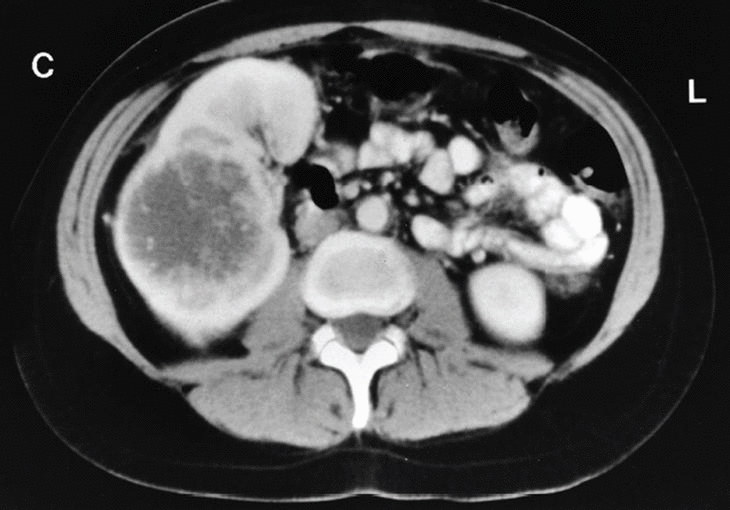

Para completar su estudio se practicó una determinación de anticuerpos e Echinococcus, toxoplasma y Yersinia que fueron negativos. En la ecografía abdominal no se apreciaban alteraciones a nivel de hígado, vía biliar o vesícula, llamando la atención una formación sólida, de estructura ecográfico-inhomogénea y 75 mm de diámetro máximo en el polo superior del riñón derecho (fig. 1). Esta imagen se confirma en la tomografía axial computarizada abdominal, que sugiere una tumoración renal con necrosis central. La vena renal es permeable y no hay adenopatías retroperitoneales (fig. 2).

Fig. 2.

Ante la presencia de enzimas hepáticas anormales, sobre todo con una separación isoenzimática estrictamente hepática, el procedimiento más eficaz es la ecografía abdominal, ya que permite diagnosticar patología obstructiva al tiempo que una participación parenquimatosa, aunque en nuestro caso las enzimas eran específicas espacio-ocupantes. Ante la demostración ecográfica de una masa renal, el paso siguiente es la tomografía computarizada, que descarta la participación hepática, la evidencia de metástasis a nivel del abdomen o pelvis, la participación de la vena renal y, por supuesto, las características anatómicas de la masa renal, que eran sugestivas de una enfermedad maligna.